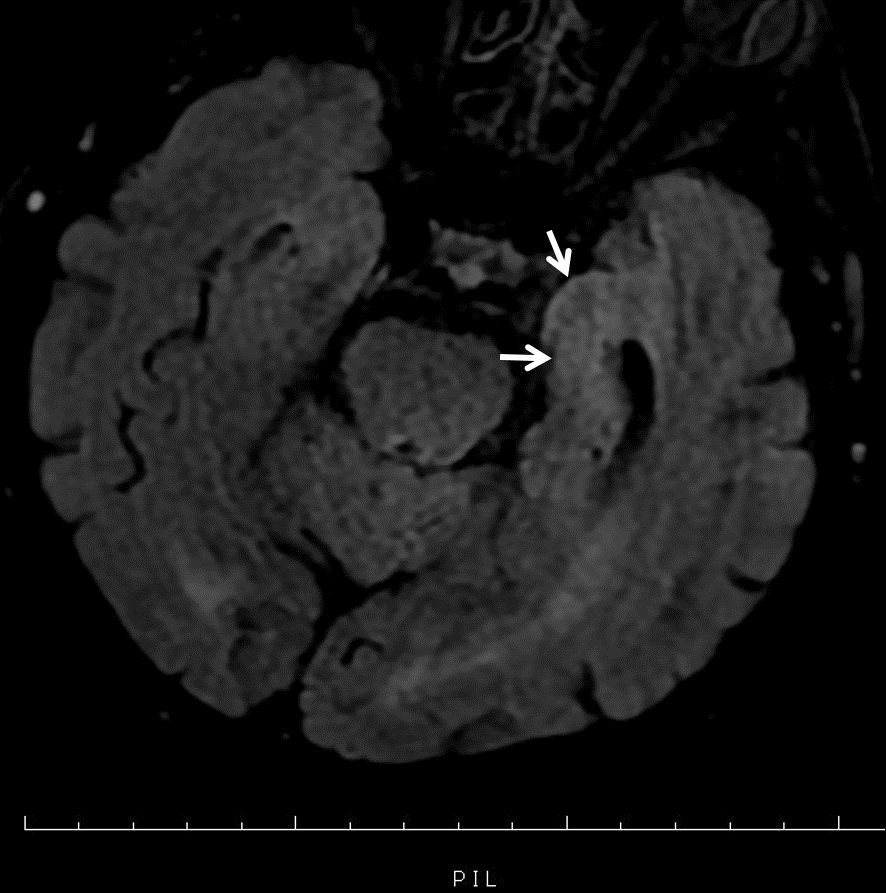

On physical examination; There is no time-place orientation, consciousness is confused, there is neck rigidity, fever is 36.1 C, blood pressure arterial: 130/80 mmHg, pulse: 102/min, saturation: 96. Other system examinations were normal. He had a history of diabetes mellitus, chronic obstructive pulmonary disease and previous corneal transplantations. It was learned that he underwent corneal transplantation 4 times before and the last transplantation was performed 1 month ago. He had been using mycophenylate mofetil 500 mg twice a day and prednisolone 16 mg once a day as immunosuppressive treatment after transplantation. Cranial magnetic resonance imaging showed T2 hyperintensity in the left medial temporal lobe (Figure 2) consistent with encephalitis.

Figure 2. Hyperintense signal in the left medial temporal lobe in magnetic resonance imaging.